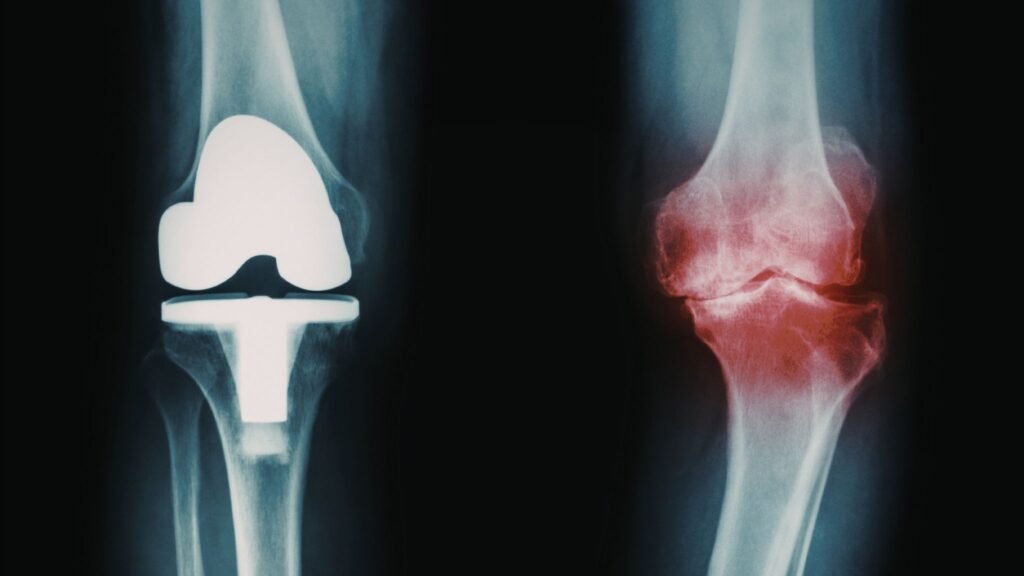

- A DHGMA aumentou o risco de osteoartrite em geral (HR = 1,72)

- Subtipos com sobrepeso e disfunção metabólica elevaram ainda mais esse risco (HR = 1,75)

- A associação foi mais evidente na osteoartrite do joelho, seguida por quadril e mãos

Publicado em 2026, o estudo demonstra uma ligação importante entre doenças hepáticas metabólicas e a osteoartrite. Além disso, os resultados mostram que fatores como obesidade e consumo de álcool podem intensificar esse risco, especialmente nas articulações mais sobrecarregadas, como o joelho.